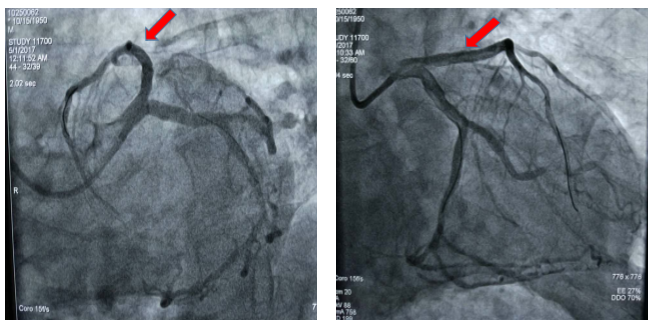

图1 患者术前冠脉造影显示冠脉血管前降支近段100%闭塞

图2 患者术后冠脉造影显示冠脉血管前降支支架治疗后完全开通